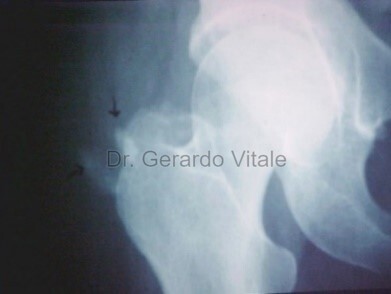

Estudios médicos que se pueden solicitar según el caso clínico son; Análisis de sangre (recuento de glóbulos blancos, marcadores inflamatorios etc.) Radiografías, Ecografía y la Resonancia Magnética pueden ayudar a distinguir las causas infecciosas de las no infecciosas.